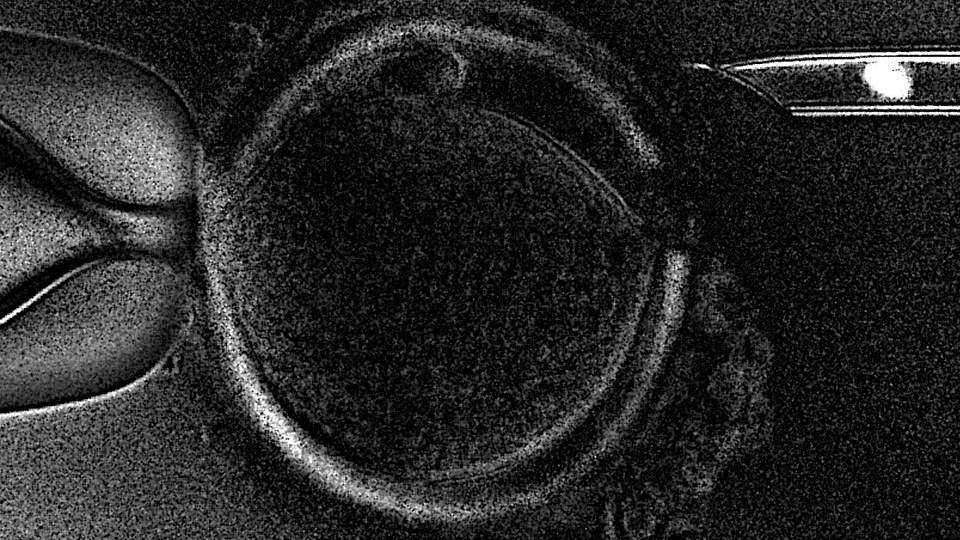

La novedad de la tecnica de la Transferencia de Huso Materno (MST, en sus siglas en ingles) es que permite que mujeres que no consiguen el embarazo con tratamientos in vitro convencionales -que usan el material ovárico de la paciente-, puedan hacerlo con la ayuda de una donante de óvulos pero sin renunciar al propio material genetico.

Esto es posible porque se extrae el huso meiótico (núcleo) de un ovocito (óvulo inmaduro) no fecundado de la paciente, dónde se encuentra el ADN, y se implanta en un ovocito sano proveniente de una donante, al cual a su vez se ha retirado previamente su núcleo.

De esta forma, el óvulo resultante contiene el material genetico de la paciente pero el resto de componentes, que tienen un papel crucial en la salida adelante del embrión, son de una donante sana.

Este óvulo es, finalmente, fecundado con el esperma de la pareja e implantado en la paciente.